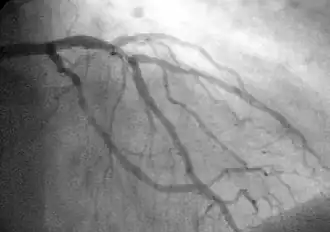

A coronary angiogram showing the circulation in the left coronary artery and its branches.

Tight, critical stenosis (95%) of the proximal LAD in a patient with Wellens' warning